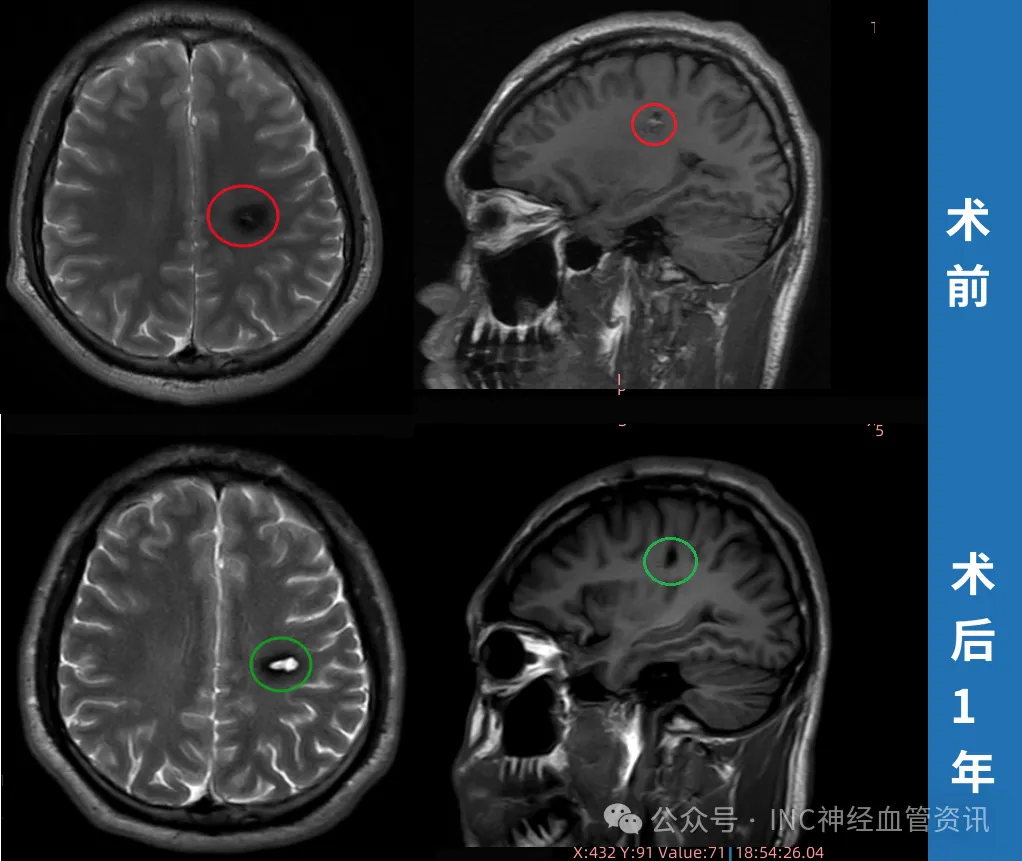

2023年3月术前MRI显示病灶体积较小,精准定位难度较大。2023年4月,通过INC中国代表处联系巴特朗菲教授进行远程咨询。教授评估认为:"通过中央前沟入路,结合神经导航和术中超声技术,可实现病灶精准切除,且不会造成新的运动功能障碍。"

2023年4月9日手术在神经导航引导下进行,巴特朗菲教授运用显微外科技术完整切除病灶。术后患者恢复良好:4天后可独立行走,2个月后恢复自行车骑行能力,1年后MRI复查显示病灶完全切除,周围组织无异常。